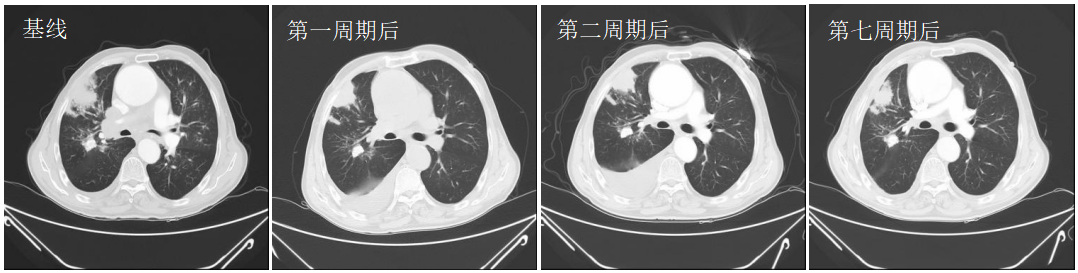

2022-02-07(第2周期治疗后)肿瘤标志物胃泌素释放肽前体测定较前明显下降(471.21pg/ml→63.38pg/ml)。复查CT:肺内病灶较前变化不大,原纵隔及右肺门肿大淋巴结,较前减小;右肺上叶新发多个结节灶,右侧少量胸腔积液,较前增多,疗效综合评估:SD。

2022-04-05(第4周期治疗后)疗效评效SD。

2022-05-19(第7周期治疗后)胸部CT:右肺占位复查,较前稍增大;纵隔及右肺门肿大淋巴结,大部分较前增大,双侧胸腔积液,两肺多个结节,考虑转移可能性大。2022-05-26完善CT引导下肺穿刺活检,病理为治疗后肿瘤性坏死,疗效综合评估:SD。